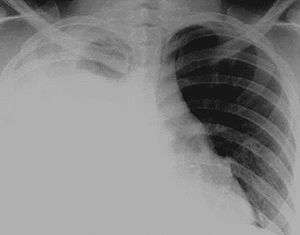

Hydrothorax is a type of pleural effusion in which serous fluid accumulates in the pleural cavity. This condition is most likely to develop secondary to congestive heart failure, but may rarely develop in patients with cirrhosis or ascites. Hepatic hydrothorax is often difficult to manage in end-stage liver failure and often fails to respond to therapy.